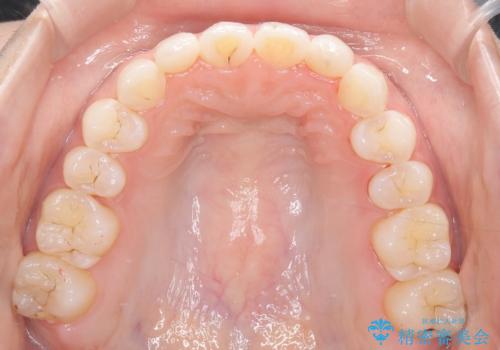

- 前歯の凸凹を主訴に来院された患者様です。

カウンセリング時に、側切歯が矮小歯であることを指摘したところ、適切な幅径での修復を希望されました。

インビザラインを用い、計画通りに歯並びを改善することができました。

矮小歯の幅径を大きくすることで、より理想的な噛み合わせを作ることができます。